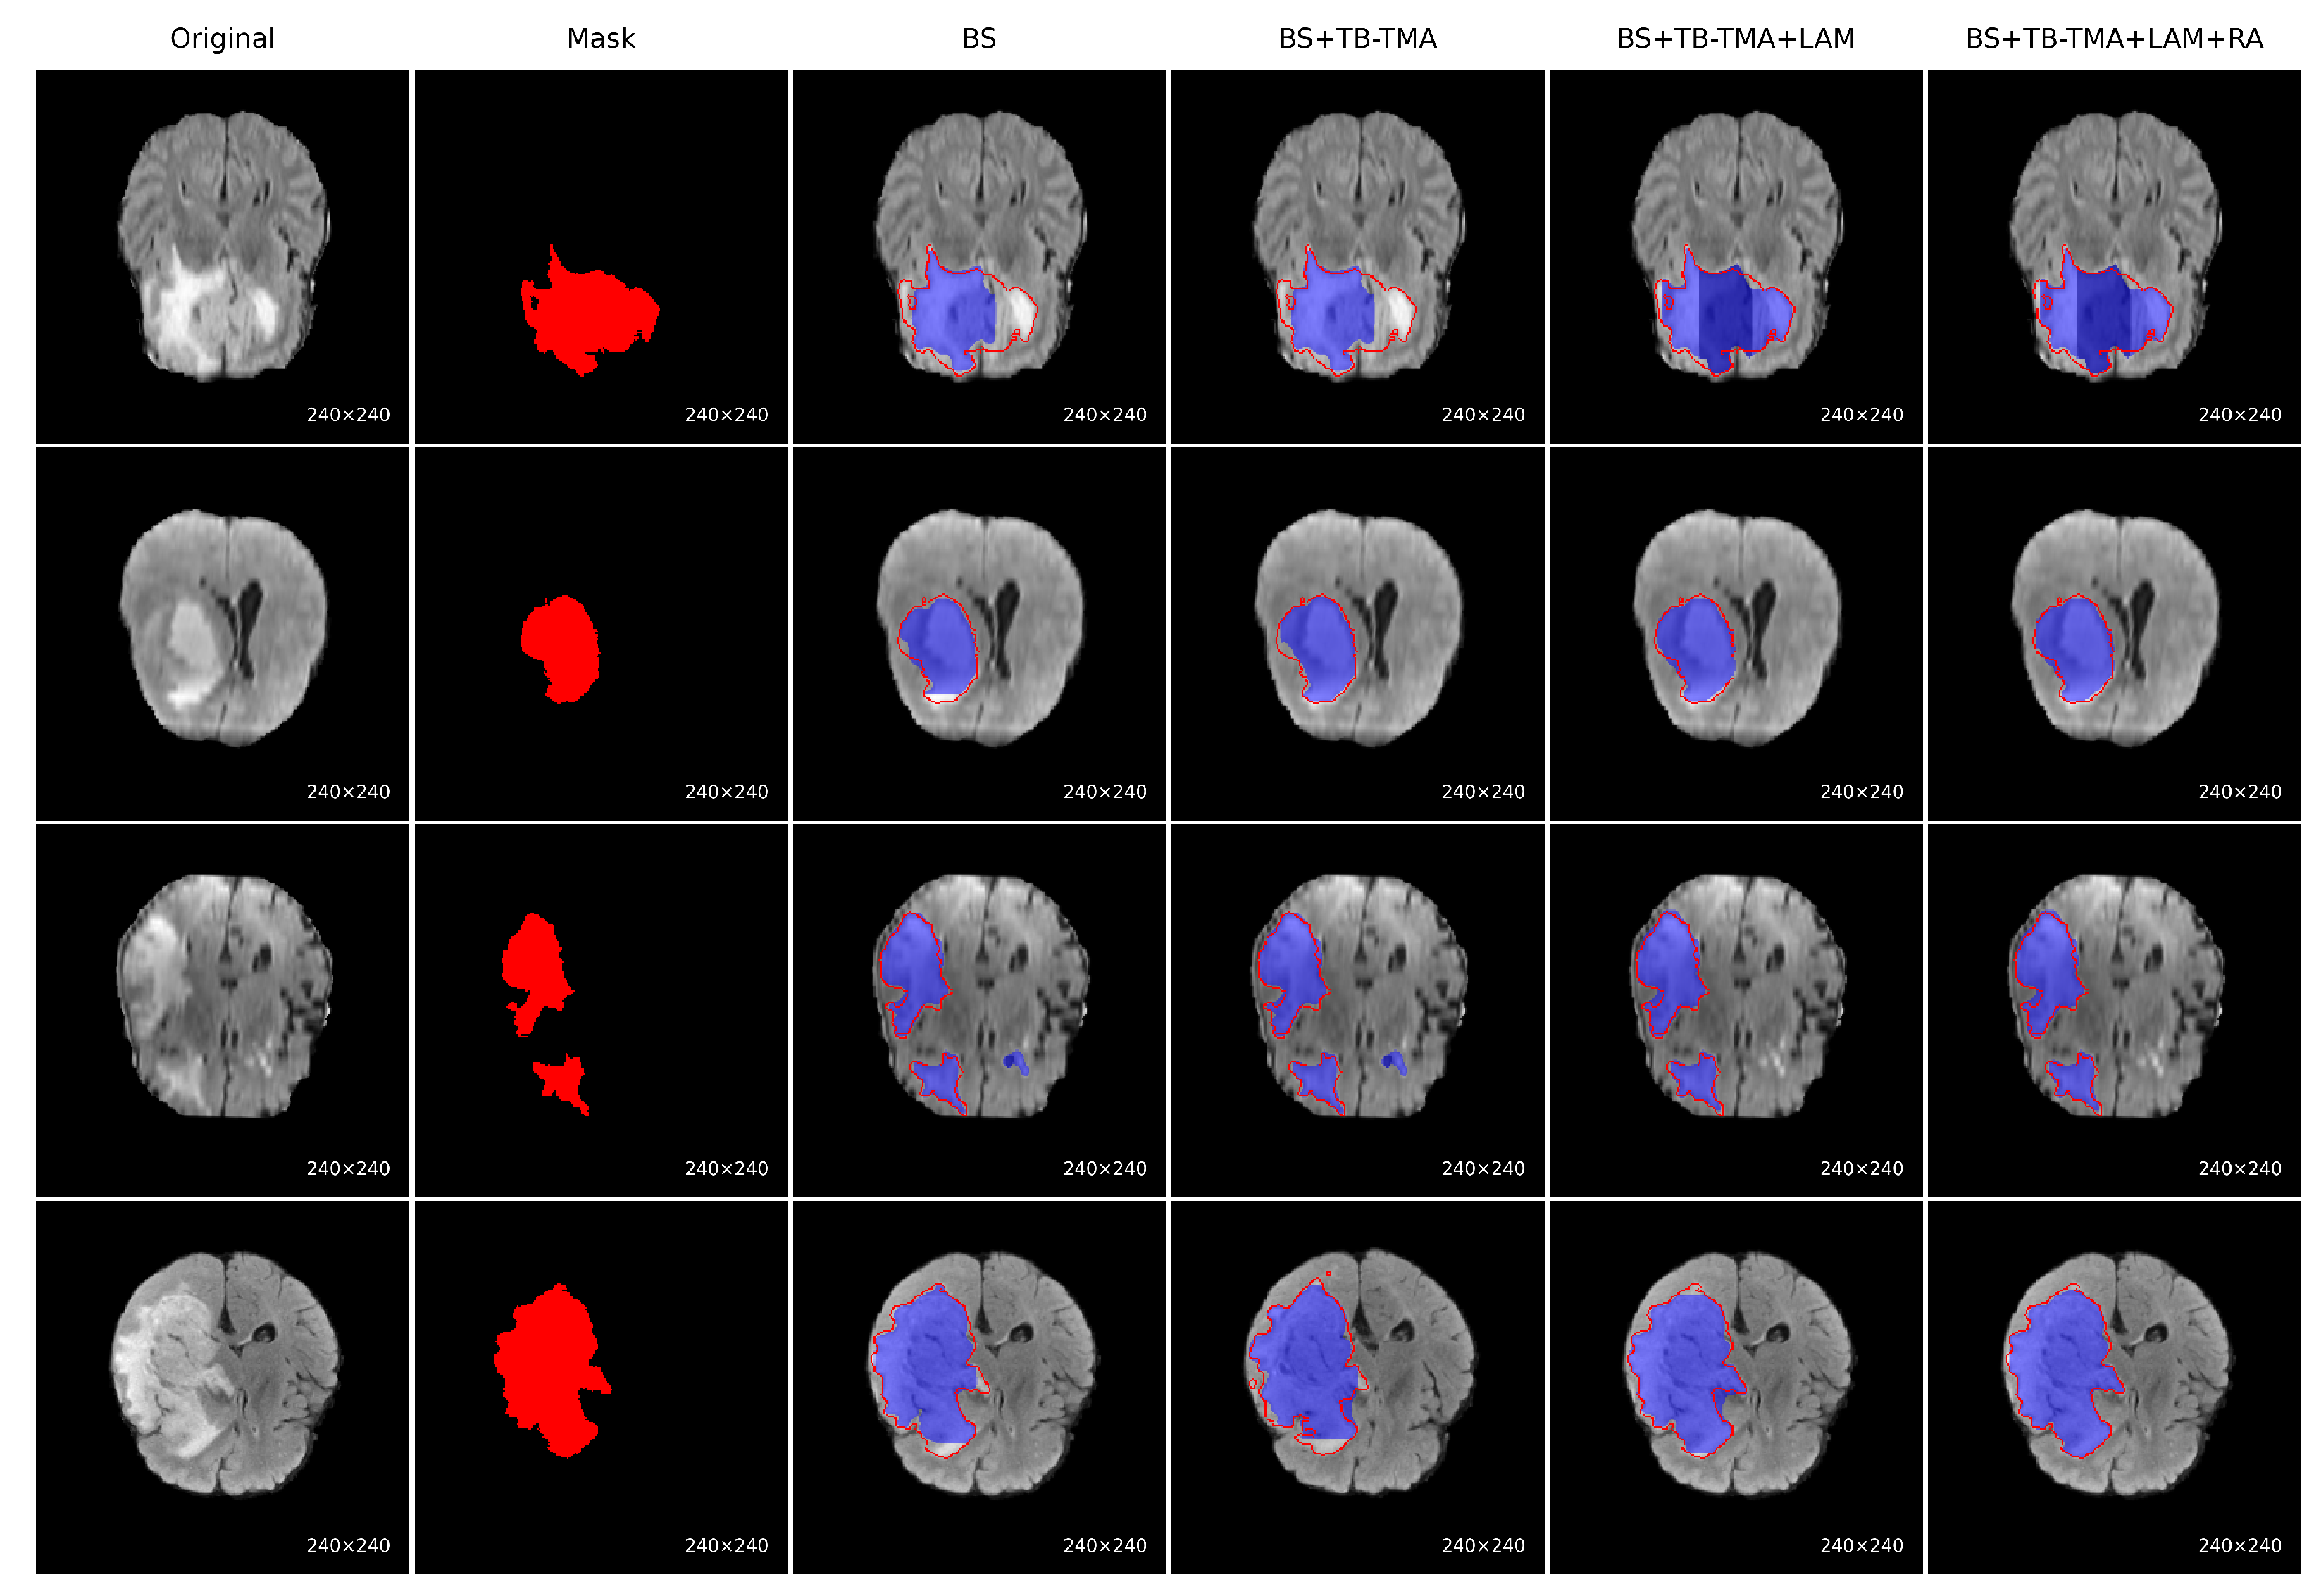

To evaluate the performance improvement of each module, we conducted a series of ablation experiments on the BraTS brain tumor segmentation task, with visual results presented for each approach, as shown in Figure 7. The baseline model (BS) showed significant issues, such as missing tumor regions and inaccurate boundaries. After incorporating the TB-TMA module, the model effectively fused unimodal and cross-modal features through a dual-branch structure and cross-attention mechanism, enhancing the model’s cross-modal representation ability and resulting in more complete tumor segmentation. Further integration of the LAM module improved the model’s multi-scale feature modeling capability, leading to better identification of large tumor areas. Finally, the RA module, with its residual structure and attention stacking, refined boundary segmentation and significantly improved the precision of edge region localization. The combined results demonstrate that the synergistic effect of these modules significantly enhances both accuracy in segmenting tumor regions and boundary detail restoration.

Figure 7. Visual comparison of ablation results on the BraTS brain tumor segmentation task. Each row represents a sample, showing the following (from left to right): the original image; ground-truth mask; baseline (BS) output; BS with TB-TMA module; BS with TB-TMA and LAM modules; and the final model with TB-TMA, LAM, and RA modules. The progressive improvements demonstrate the effectiveness of each proposed component in enhancing segmentation completeness and boundary accuracy. In the Mask column, the red regions represent the true tumor segmentation. In all predicted results, the blue areas indicate the predicted segmentation, while the red contour lines overlay the ground-truth boundaries for comparison.